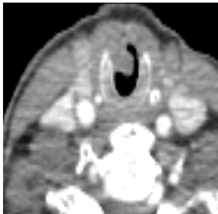

A 69-year-old lady presented with a constant burning sensation in her tongue of three months’ duration. She was found to have an extremely nodular left tongue, especially at the tip and lateral surface, which was exquisitely tender upon palpation. Diagnosis was uncertain, thus MRI was performed, demonstrating a 2.2cm by 1.7cm lobulated left-side tongue mass of high signal intensity on short T1-inversion recovery (STIR) images (Figure 1). It did not extend into the floor of the mouth and there was no abnormal adenopathy. A biopsy was performed, providing a histological diagnosis of ACC. Staging CT chest and abdomen with contrast showed a non-specific solitary 9.5cm pulmonary nodule peripherally at the left lung base with no mediastinal or hilar adenopathy. It was elected in the head and neck cancer multidisciplinary team meeting that she have local excision of the tumor. A partial glossectomy with resection of tumor was performed utilizing a carbon dioxide laser (10watts continuous). During the procedure the ducts were avoided and preserved.

Figure 1 Axial MRI Scan Showing a 2.2 Cm by 1.7 Cm Lobulated Left-Side Tongue Mass of High Signal Intensity on STIR Images Which Slightly Crosses the Midline Anteriorly.